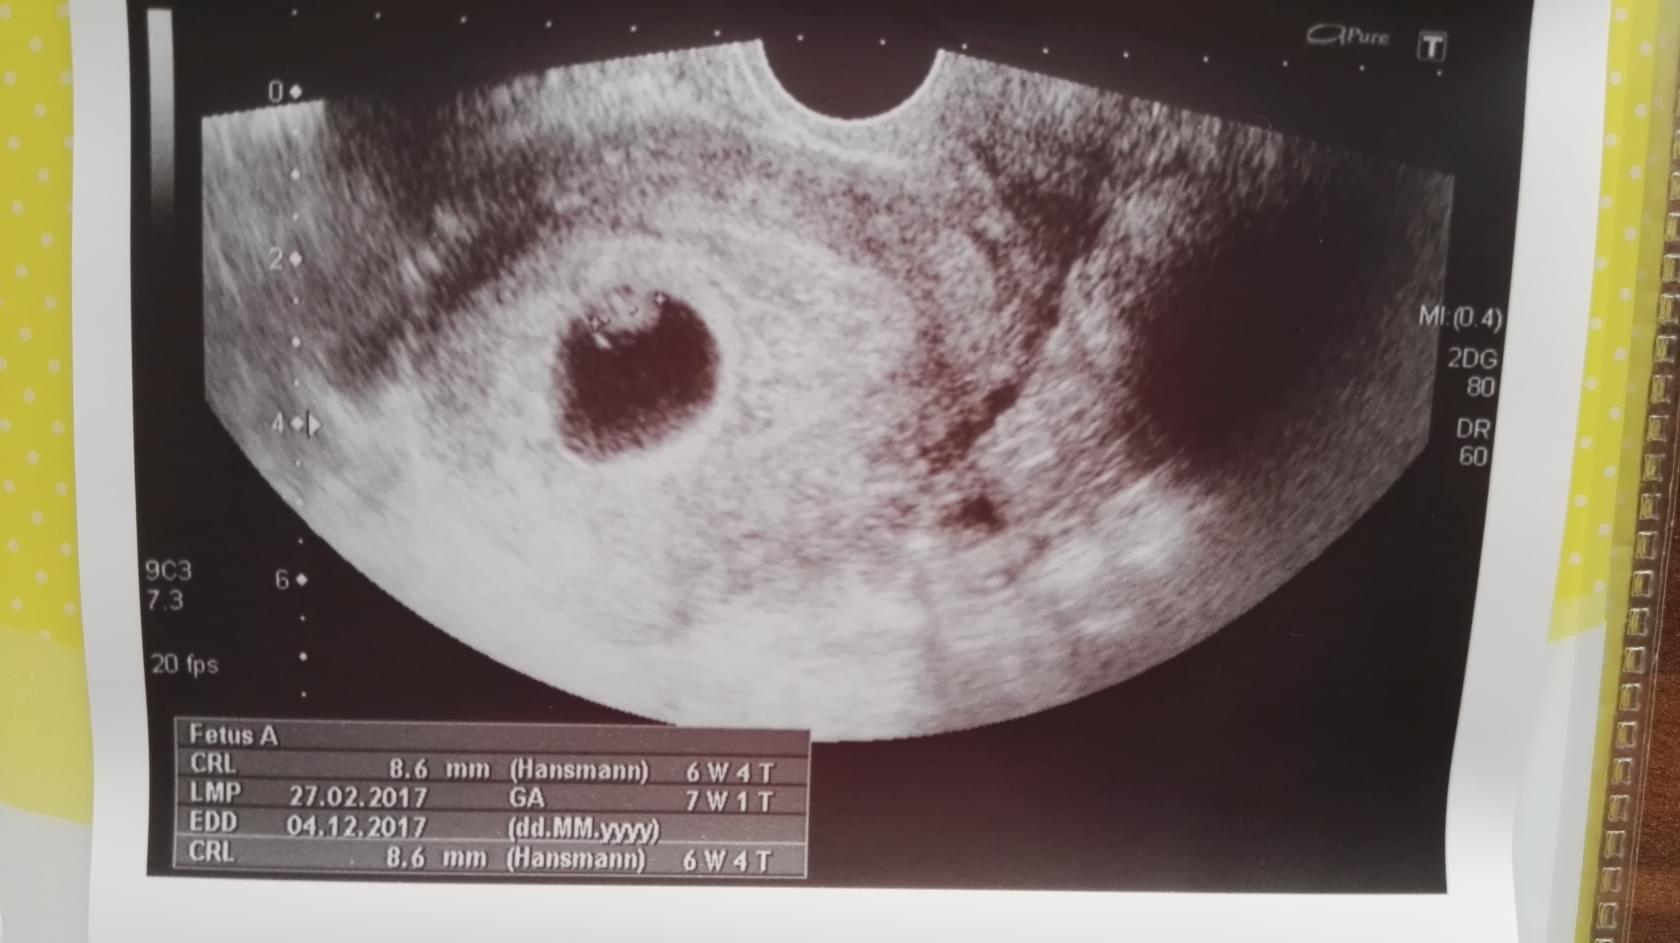

W zeszły wtorek bylo0.50cm, więc Fasola urosła 7 mm. A Ty się Kochana nie denerwuj, każde dzidzi rośnie w swoim tempie :* lekarz mówił Ci ze jest ok to znaczy że jest okej spokojnie!

No i już się zdenerwowałam...dobra to jeszcze raz. Święta i nas spokojnie, w piątek przed miałam wizytę, noszę w brzuszku 1,5 cm szczęścia, wyniki ok tylko tarczyca blisko granicy więc dostałam tab. A i termin mam na 30 listopada...ale mam nadzieję że mogę zostać: )